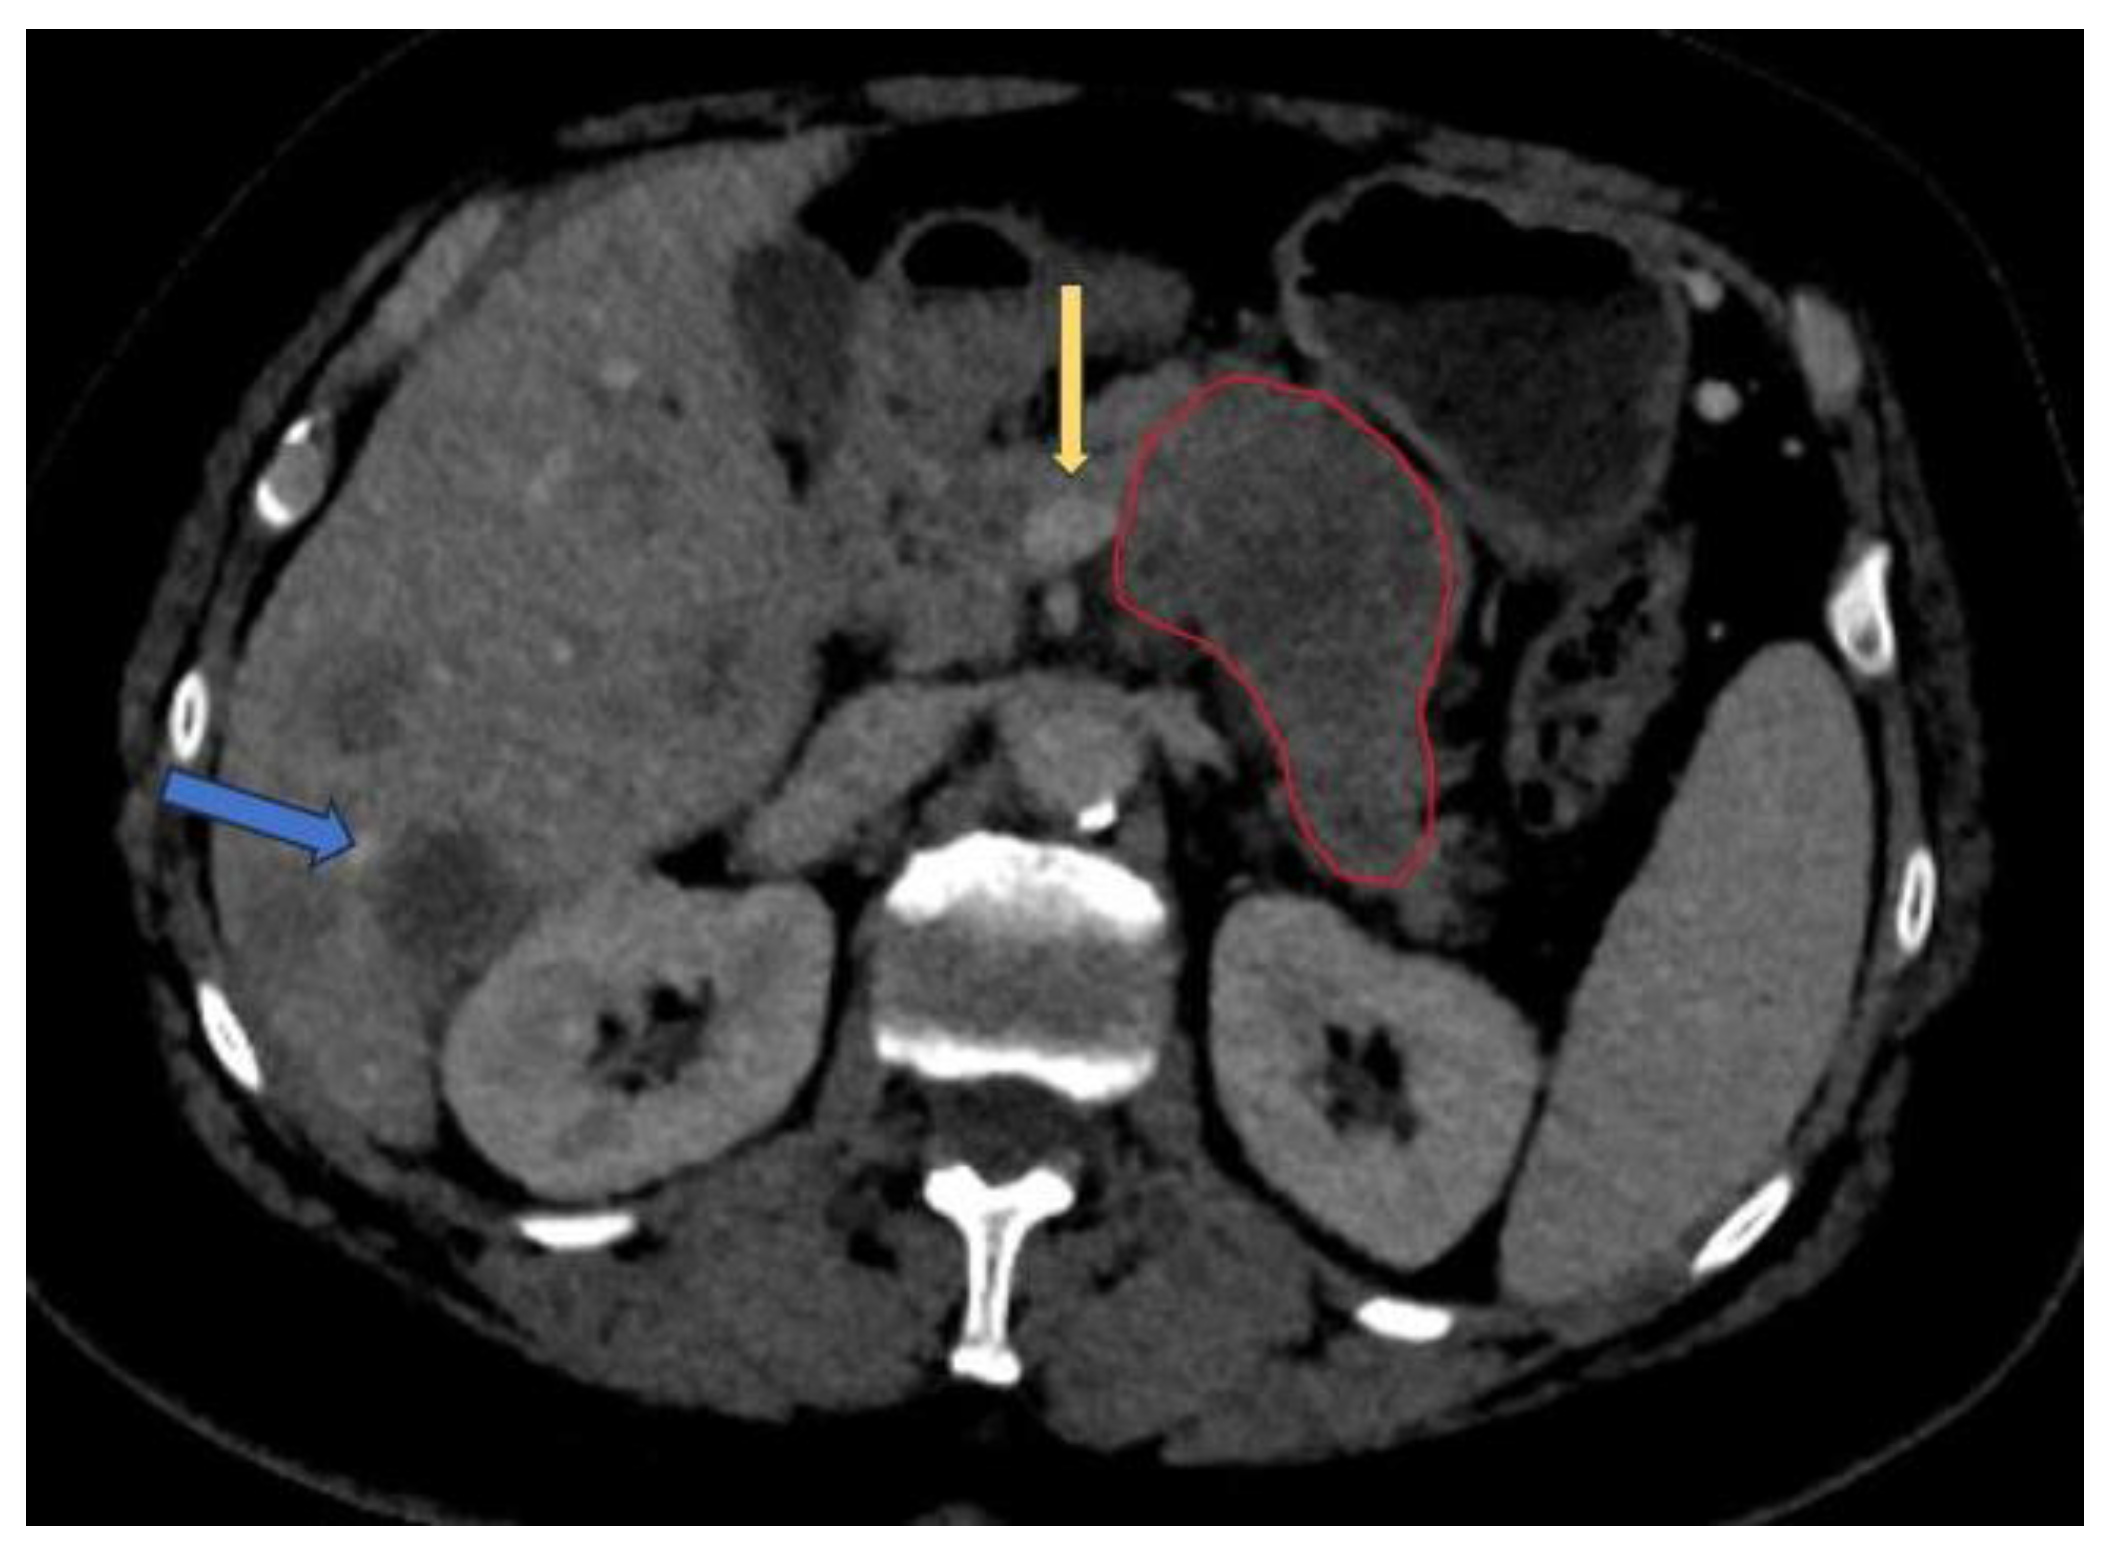

Contrast-enhanced computer tomography (CECT) represents the modality of choice to evaluate PDAC due to its ability to define the vascular involvement of the major blood vessels and to detect the presence of metastases (mainly in the liver, lung and peritoneum). The National Comprehensive Cancer Network (NCCN) guideline recommends the use of CECT as the preferred modality for evaluation at presentation and 4 weeks before surgery and following neoadjuvant treatment for staging and assessment of resectability status[24]. The typical pancreatic CECT protocol is composed of dual-phase acquisition after intravenous contrast medium administration with a pancreatic phase around 35-40 seconds after contrast agent injection and a portal venous phase after a 65 to 70 seconds delay [25]. The advantage of the pancreatic phase consists of better contrast between the increased enhancement of the pancreatic normal parenchyma and the hypoattenuating adenocarcinoma. The portal venous phase allows an easier detection of the hepatic metastases and venous thrombus. One way to improve the enhancement of pancreatic parenchyma and adjacent blood vessels is to use a saline flush in addition to power injection[26]. Resectability criteria are shown in Table 1 [27]. An example of PDAC diagnosed at CECT is shown in Figure 3[24].

Figure 2. Portal venous phase CT: pancreatic adenocarcinoma involving the corporeal region (red circle) with less than 180° contact with superior mesentery vein (yellow arrow). Multiple liver metastases noted (blue arrow).